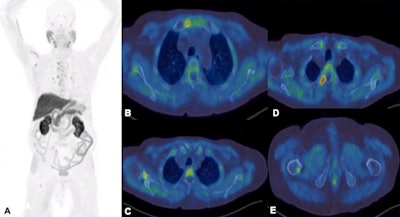

F-18 choline tracers are taken into cells by choline transporters. They are subsequently phosphorylated by choline kinase, which is overexpressed in tumors, and finally the tracers are incorporated into cell membranes. They can identify skeletal, marrow-based, and extraskeletal disease, and they have high sensitivity and specificity, for instance compared with a bone scan, and can be useful in assessing treatment response and restaging, the authors wrote.

F-18 choline PET-CT examination. A: MIP images show increased tracer uptake in the mediastinum, right axilla and right femur in a patient with prostate cancer. B-E: There is focal increased tracer uptake with the sclerotic lesions in the sternum, right scapula, right transverse process of T3 vertebra, right femur on the fused transaxial PET-CT. Low grade tracer uptake within the mediastinal and hilar nodes are suggestive of reactive/inflammatory changes.However, the sensitivity of the test is influenced by prostate-specific antigen (PSA) levels, and sensitivity increases with higher PSA levels. Also, sensitivity -- and therefore detection rate -- of microcarcinoma is limited by partial volume effect, negative scans do not rule out metastasis, and uptake in densely sclerotic bone lesions is inconsistent, especially after therapy. False positives may occur in recent traumas and fractures.